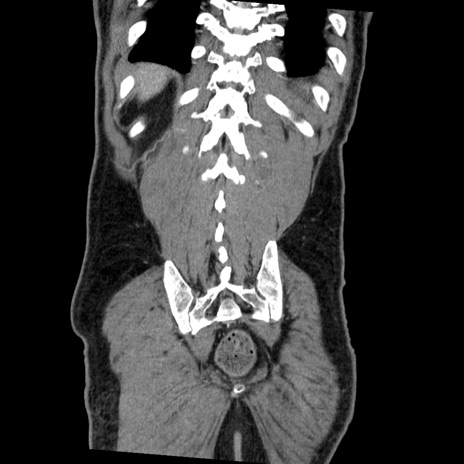

症例22(冠状断像)

【症例】50歳代男性

【主訴】腹痛

【現病歴】AVMからの被殻出血のため回復期リハ病棟入院中。 本日午後3時頃急に下腹部痛が出現した。

【既往歴】AVM、被殻出血、虫垂炎、高血圧

【身体所見】意識晴明、左半身不全麻痺、会話の理解は良好、36.5°C、腹部:膨隆、全体に板状硬、下腹部正中に圧痛点あり、反跳痛-、筋性防御不明、右下腹部にope scar

【データ】WBC 9400、CRP 0.06